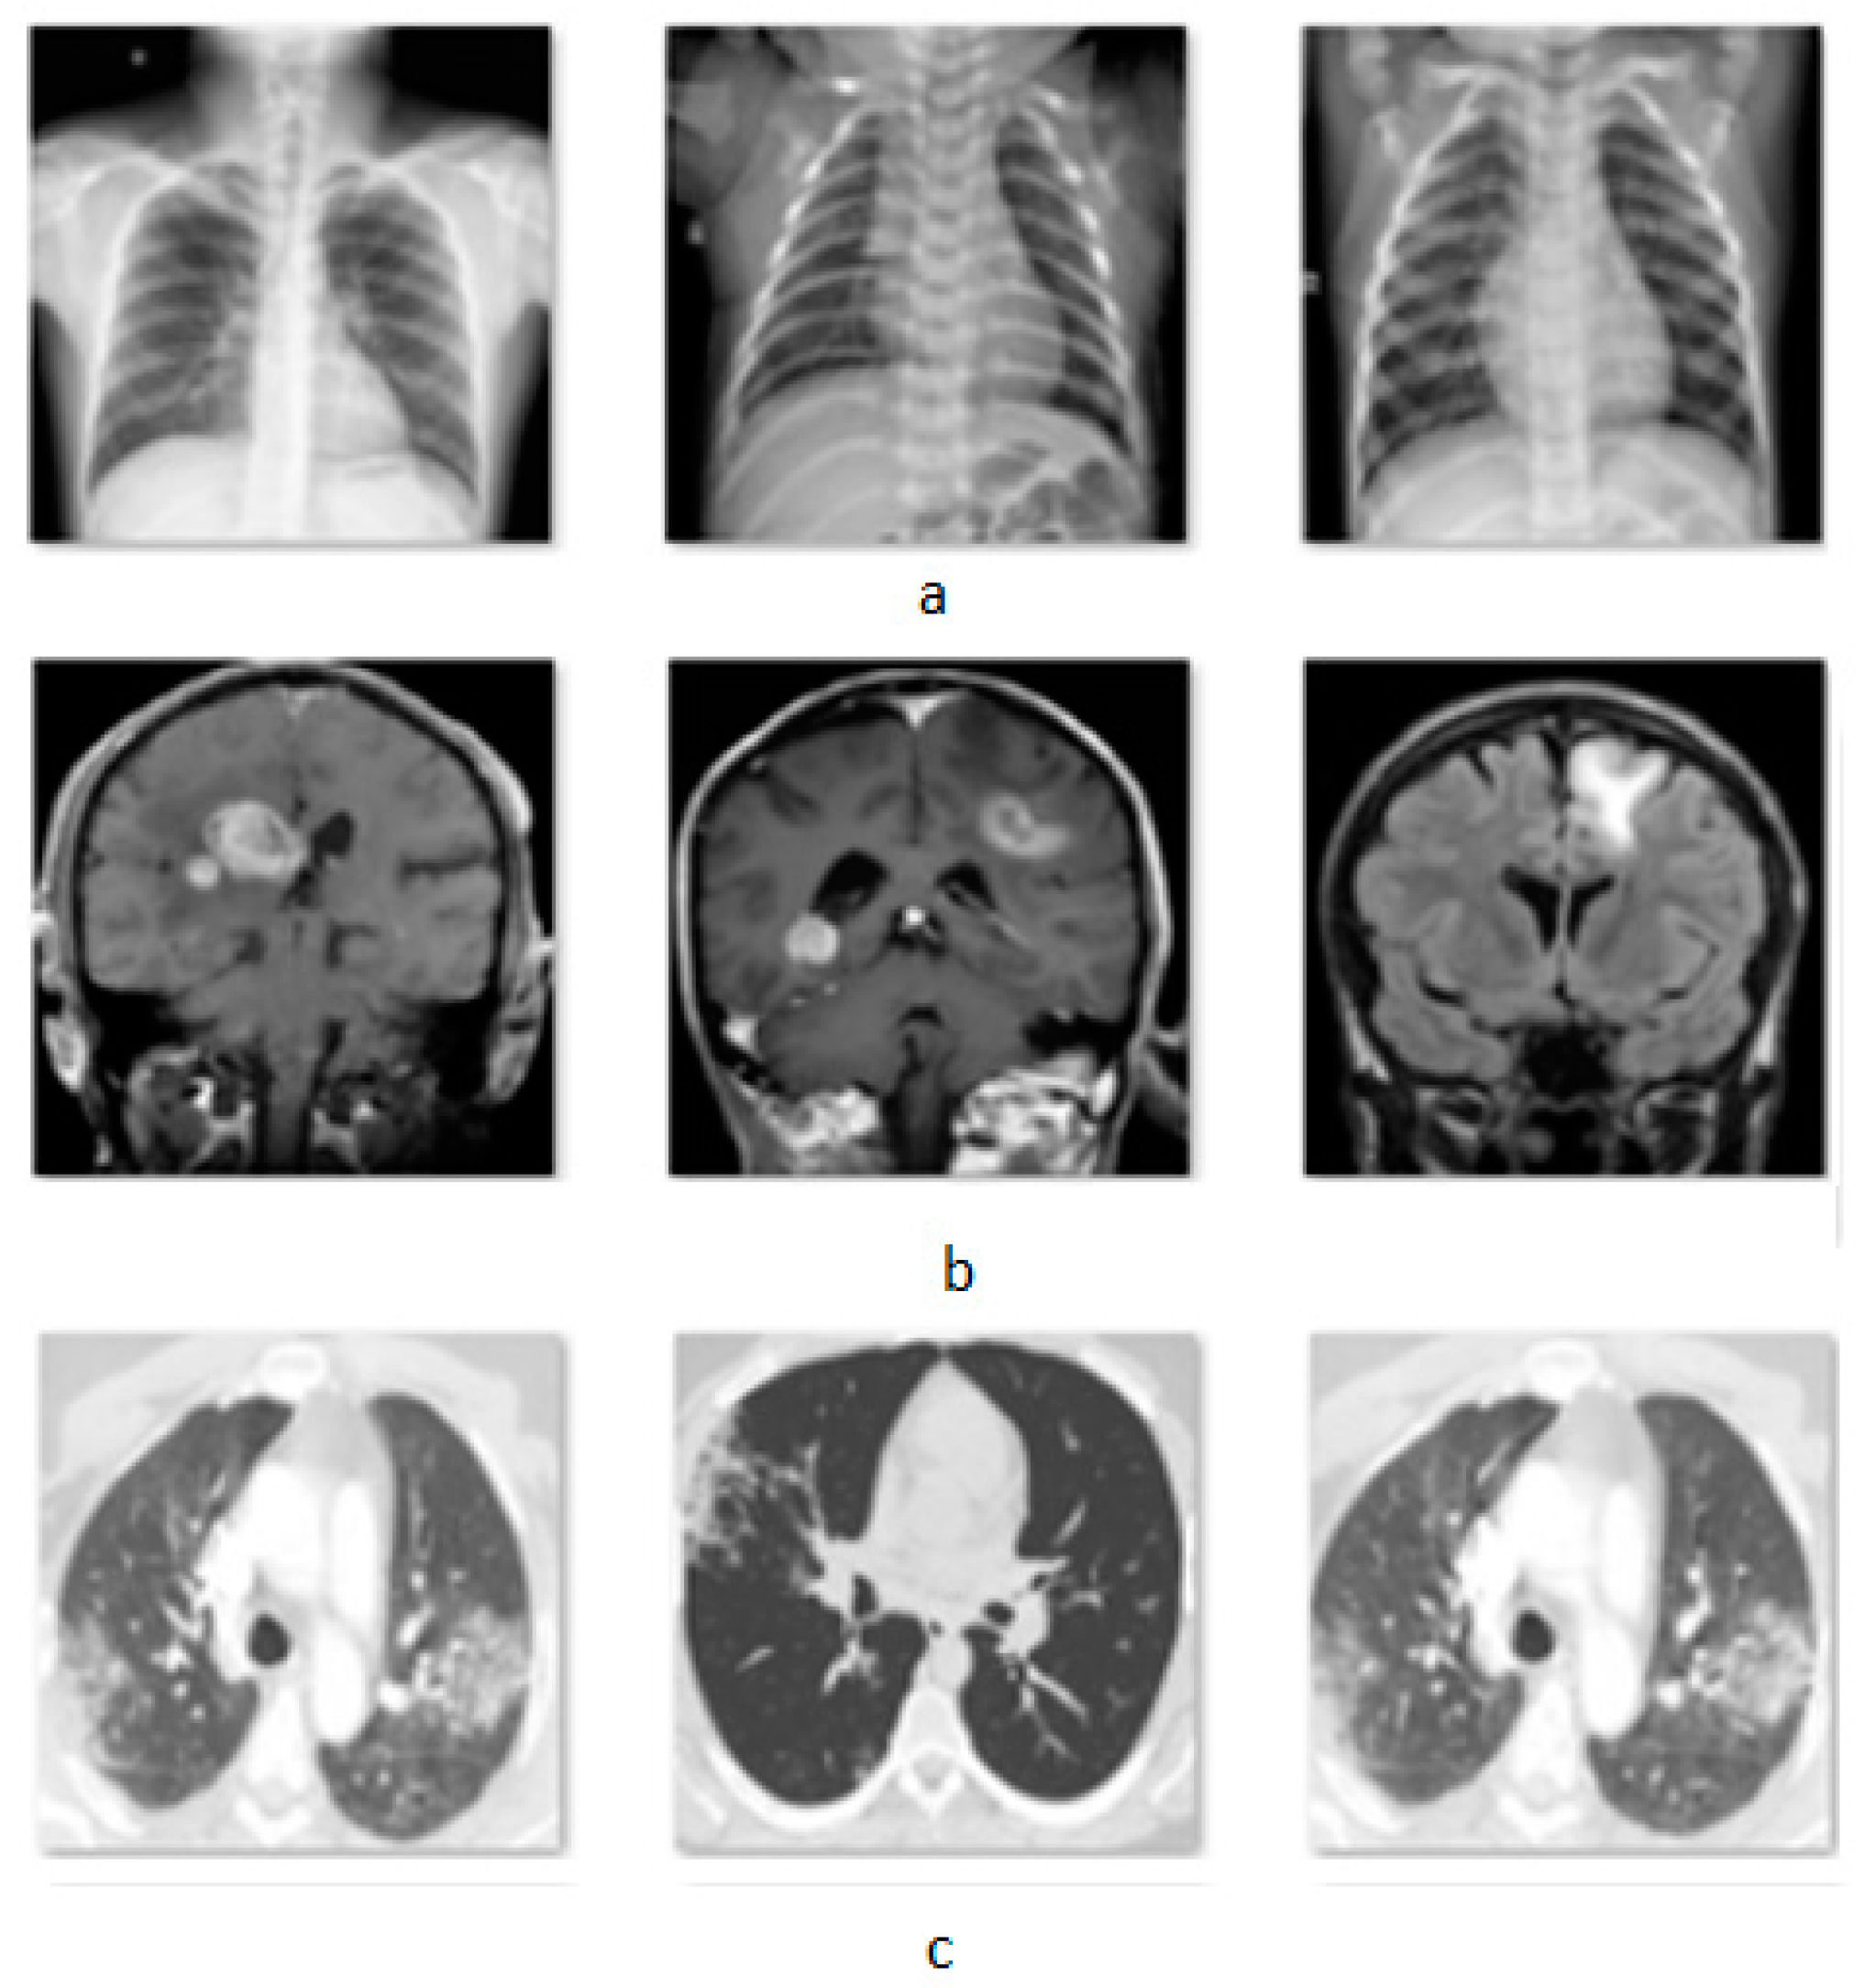

4.1. Datasets